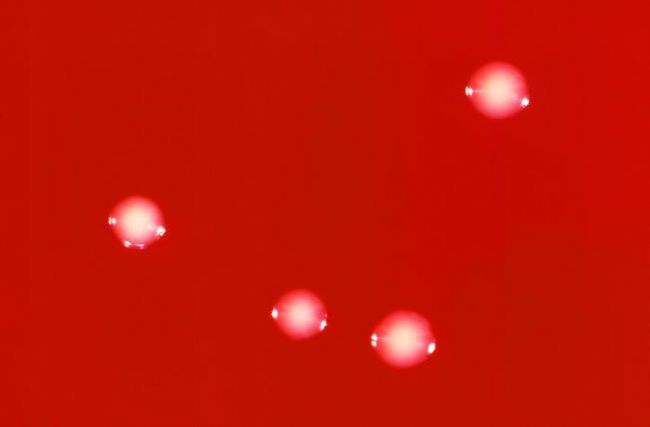

血瓊脂平板上形成灰白色、有乳光、表面光滑,邊緣整齊、直徑0.5—0.75mm的細小菌落。